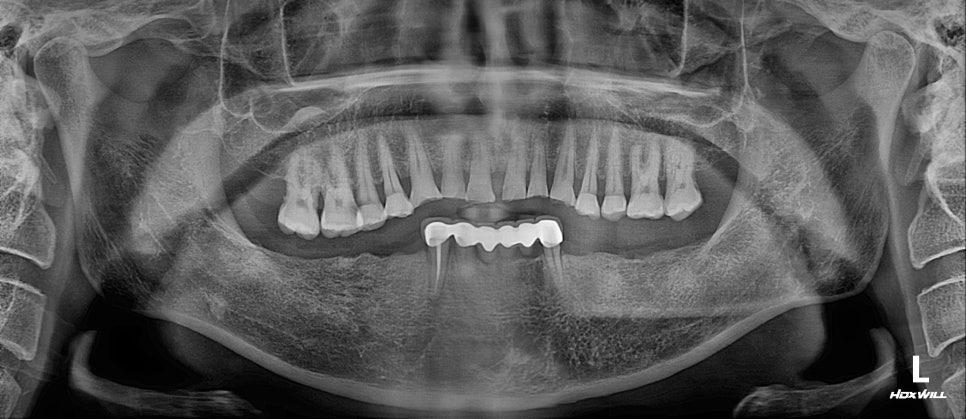

내원하셨던 환자분의

파노라마 방사선사진입니다. ^^

아래 어금니를 상실한 후 오래 방치하여

위 어금니가 내려와 교합이 무너진 상태로

내원해 주셨는데요..!

이렇게 치아를 발치한 후

치료의 최적기를 놓쳐 방치한다면

맞물리는 치아가 없는 치아들은 점점 내려오게 되어

교합이 무너지기 마련인데요!

이렇게 위 어금니들이 아래로 점점 내려오는 것을

“치아 정출“이라고 부릅니다.